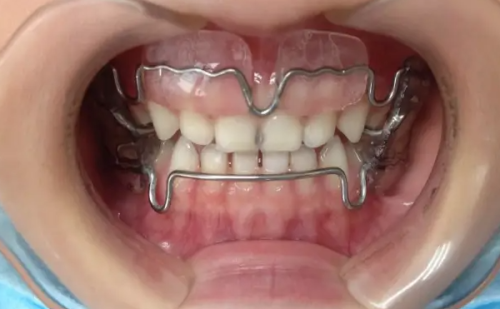

技术方面,成都新桥口腔目前注册医生200余名,其中包含多名华 西技术人才,他们不仅亲和力强,而且医术高明,能够根据患者的困扰快速找到问题所在,并制定出合理的方案进行治疗。尤其是对于种植牙和牙齿矫正项目,成都新桥口腔掌握有大量的临床成功数据,目前正畸实例3W +,种植牙实例10W +。除了常规的治疗技术外,他们也攻克了多项高难度手术,有牙齿问题的可以放心选择。收费上,作为一家有着多年经验的高品质牙科,成都新桥口腔在收费方面是严格按照卫生局标准执行的,收费公正合理透明,没有隐形消费,不用担心会有多收费或乱收费现象。

绝活上,在牙齿矫正和牙齿种植领域,新桥口腔在整个西部地区都是佼佼者,它是“隐适美”“时代天使”等大牌隐形矫正版牌以及“士卓曼”“诺贝尔”等高端种植体品牌的临床示范基地。医生团队上,新桥口腔有将近200名口腔医生,都是国内有名口腔院校毕业的精英,各个专科还有华 西口腔的骨干医生坐镇,技术水平完全不用担心。

服务和环境上,患者们普遍感受到了温馨和贴心的服务。价格上,患者们普遍反映价格透明,性价比特别高。而且相比于其他口腔医院,这里的价格真的特别合理。还有特别多患者分享了治疗前后的对比,比如年轻女士小美之前因为牙齿不齐特别自卑,到新桥口腔医院做了矫正,现在牙齿整齐多了,人也自信了不少。